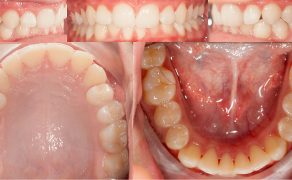

Cel. Celem pracy jest opis terapii ortodontycznej i czynnościowej pacjenta w późnym okresie uzębienia mlecznego, u którego rozpoznano: II klasę zębową i szkieletową podgrupy 2, brachycefaliczny typ wzrostu z wklęsłym profilem, ekstruzją górnych siekaczy centralnych i wychyleniem siekacza bocznego szczęki, nadmiernym napięciem mięśni żwaczy, parafunkcją zaciskania zębów i brakiem miejsca na stałe kły górne.

Opis przypadku. Artykuł opisuje leczenie 11-letniego pacjenta w późnym okresie uzębienia mlecznego, u którego rozpoznano: II klasę zębową i szkieletową podgrupy 2, brachycefaliczny typ wzrostu z wklęsłym profilem, ekstruzją górnych siekaczy centralnych i wychyleniem siekacza bocznego szczęki. W leczeniu zastosowano płytkę górną Schwarza ze śrubą trójkierunkową oraz urządzenie odciążające MFS złożone z relaksatora mięśniowego i płytki nagryzowej. Urządzenie odciążające jest efektywnym uzupełnieniem terapii ortodontycznej, wymusza długotrwałą pożądaną w terapii pracę mięśni zespołu ustno-twarzowego.